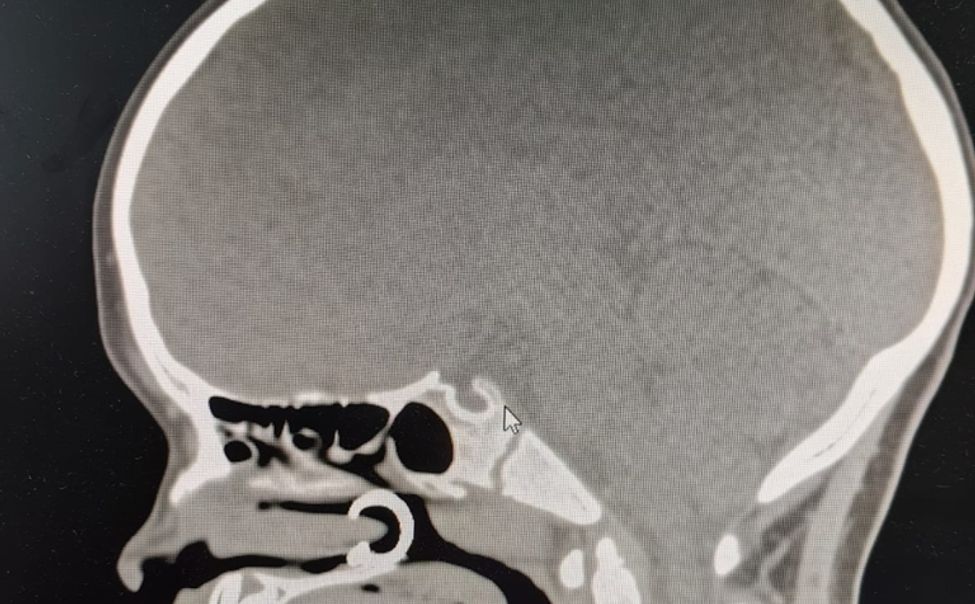

В приемно-диагностическое отделение Республиканской детской клинической больницы за медицинской помощью обратились подростки с пулевыми ранениями.

Ежедневно в отделение оториноларингологии и челюстно-лицевой хирургии Республиканской детской клинической больницы обращаются маленькие пациенты с родителями, которые, к сожалению, не могут обойтись без помощи специалистов.